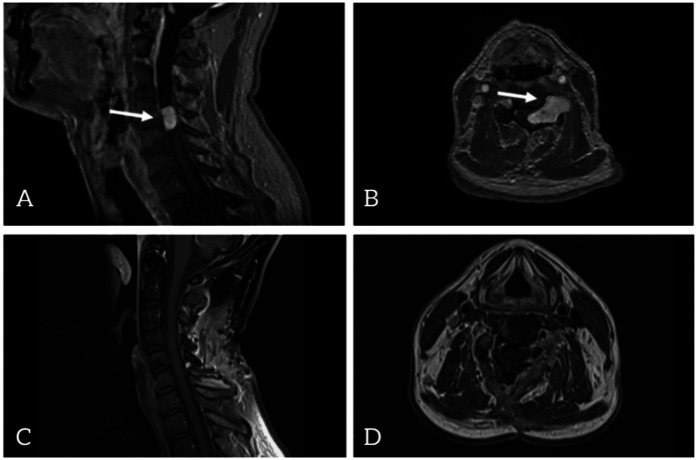

Case presentation: We present the case of a 46-year-old Caucasian male who underwent surgery for an intra- and extraspinal cervical mass lesion at the C4/5 level on the left side. Immunohistochemical analysis confirmed the diagnosis of MMNSTs. The patient initially presented with ataxia, left-sided weakness, and hemihypesthesia. Magnetic resonance imaging of the cervical spine revealed a left intra- and extraspinal homogeneous contrast-enhancing mass at the C4/C5 level. After the first intraspinal partial resection, the diagnosis of MMNST was established. Gross-total resection is highly recommended in nearly all cases in the literature, followed by adjuvant radiotherapy or chemotherapy in selected cases to prevent metastases, which occur in 15%-42% of cases. The patient postponed the second neurosurgical intervention and declined adjuvant radiotherapy. At 18 months after gross total resection, no recurrent tumor was detected by MRI.